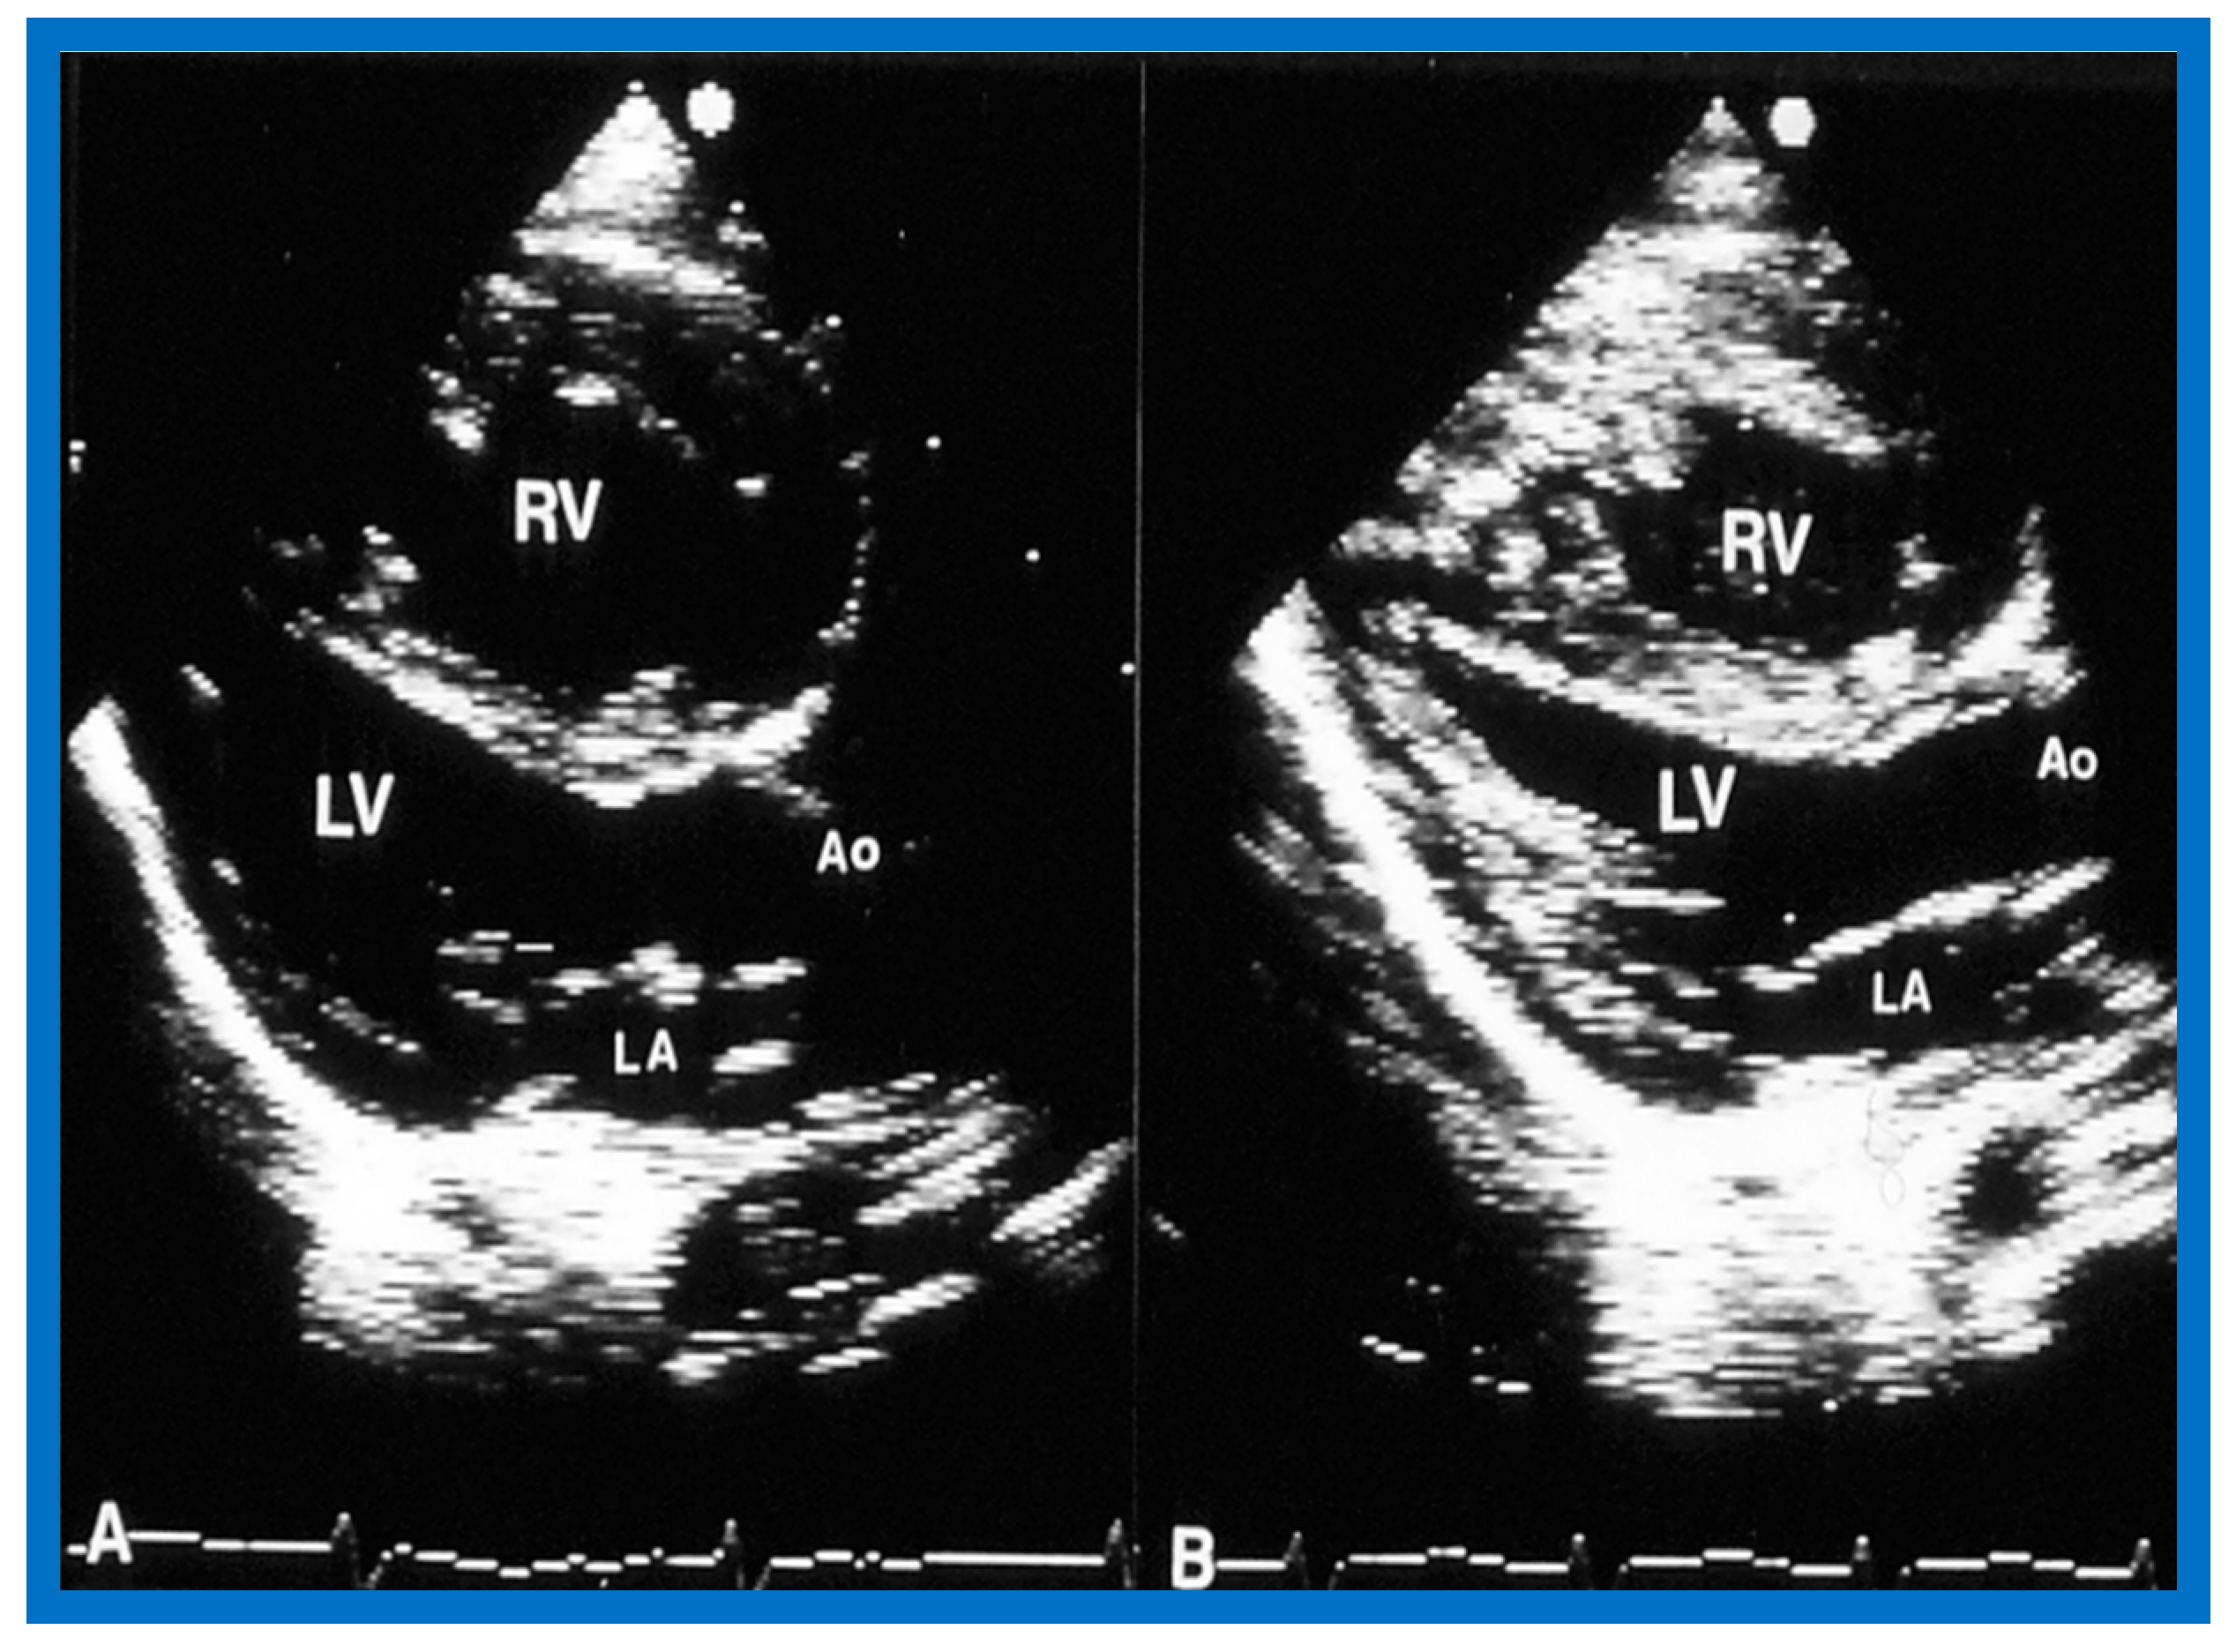

6.2.1. Residual Gradients

6.2.2. Ventricular Dimensions and Function

6.2.3. Re-Interventions and Actuarial Event-Free Rates